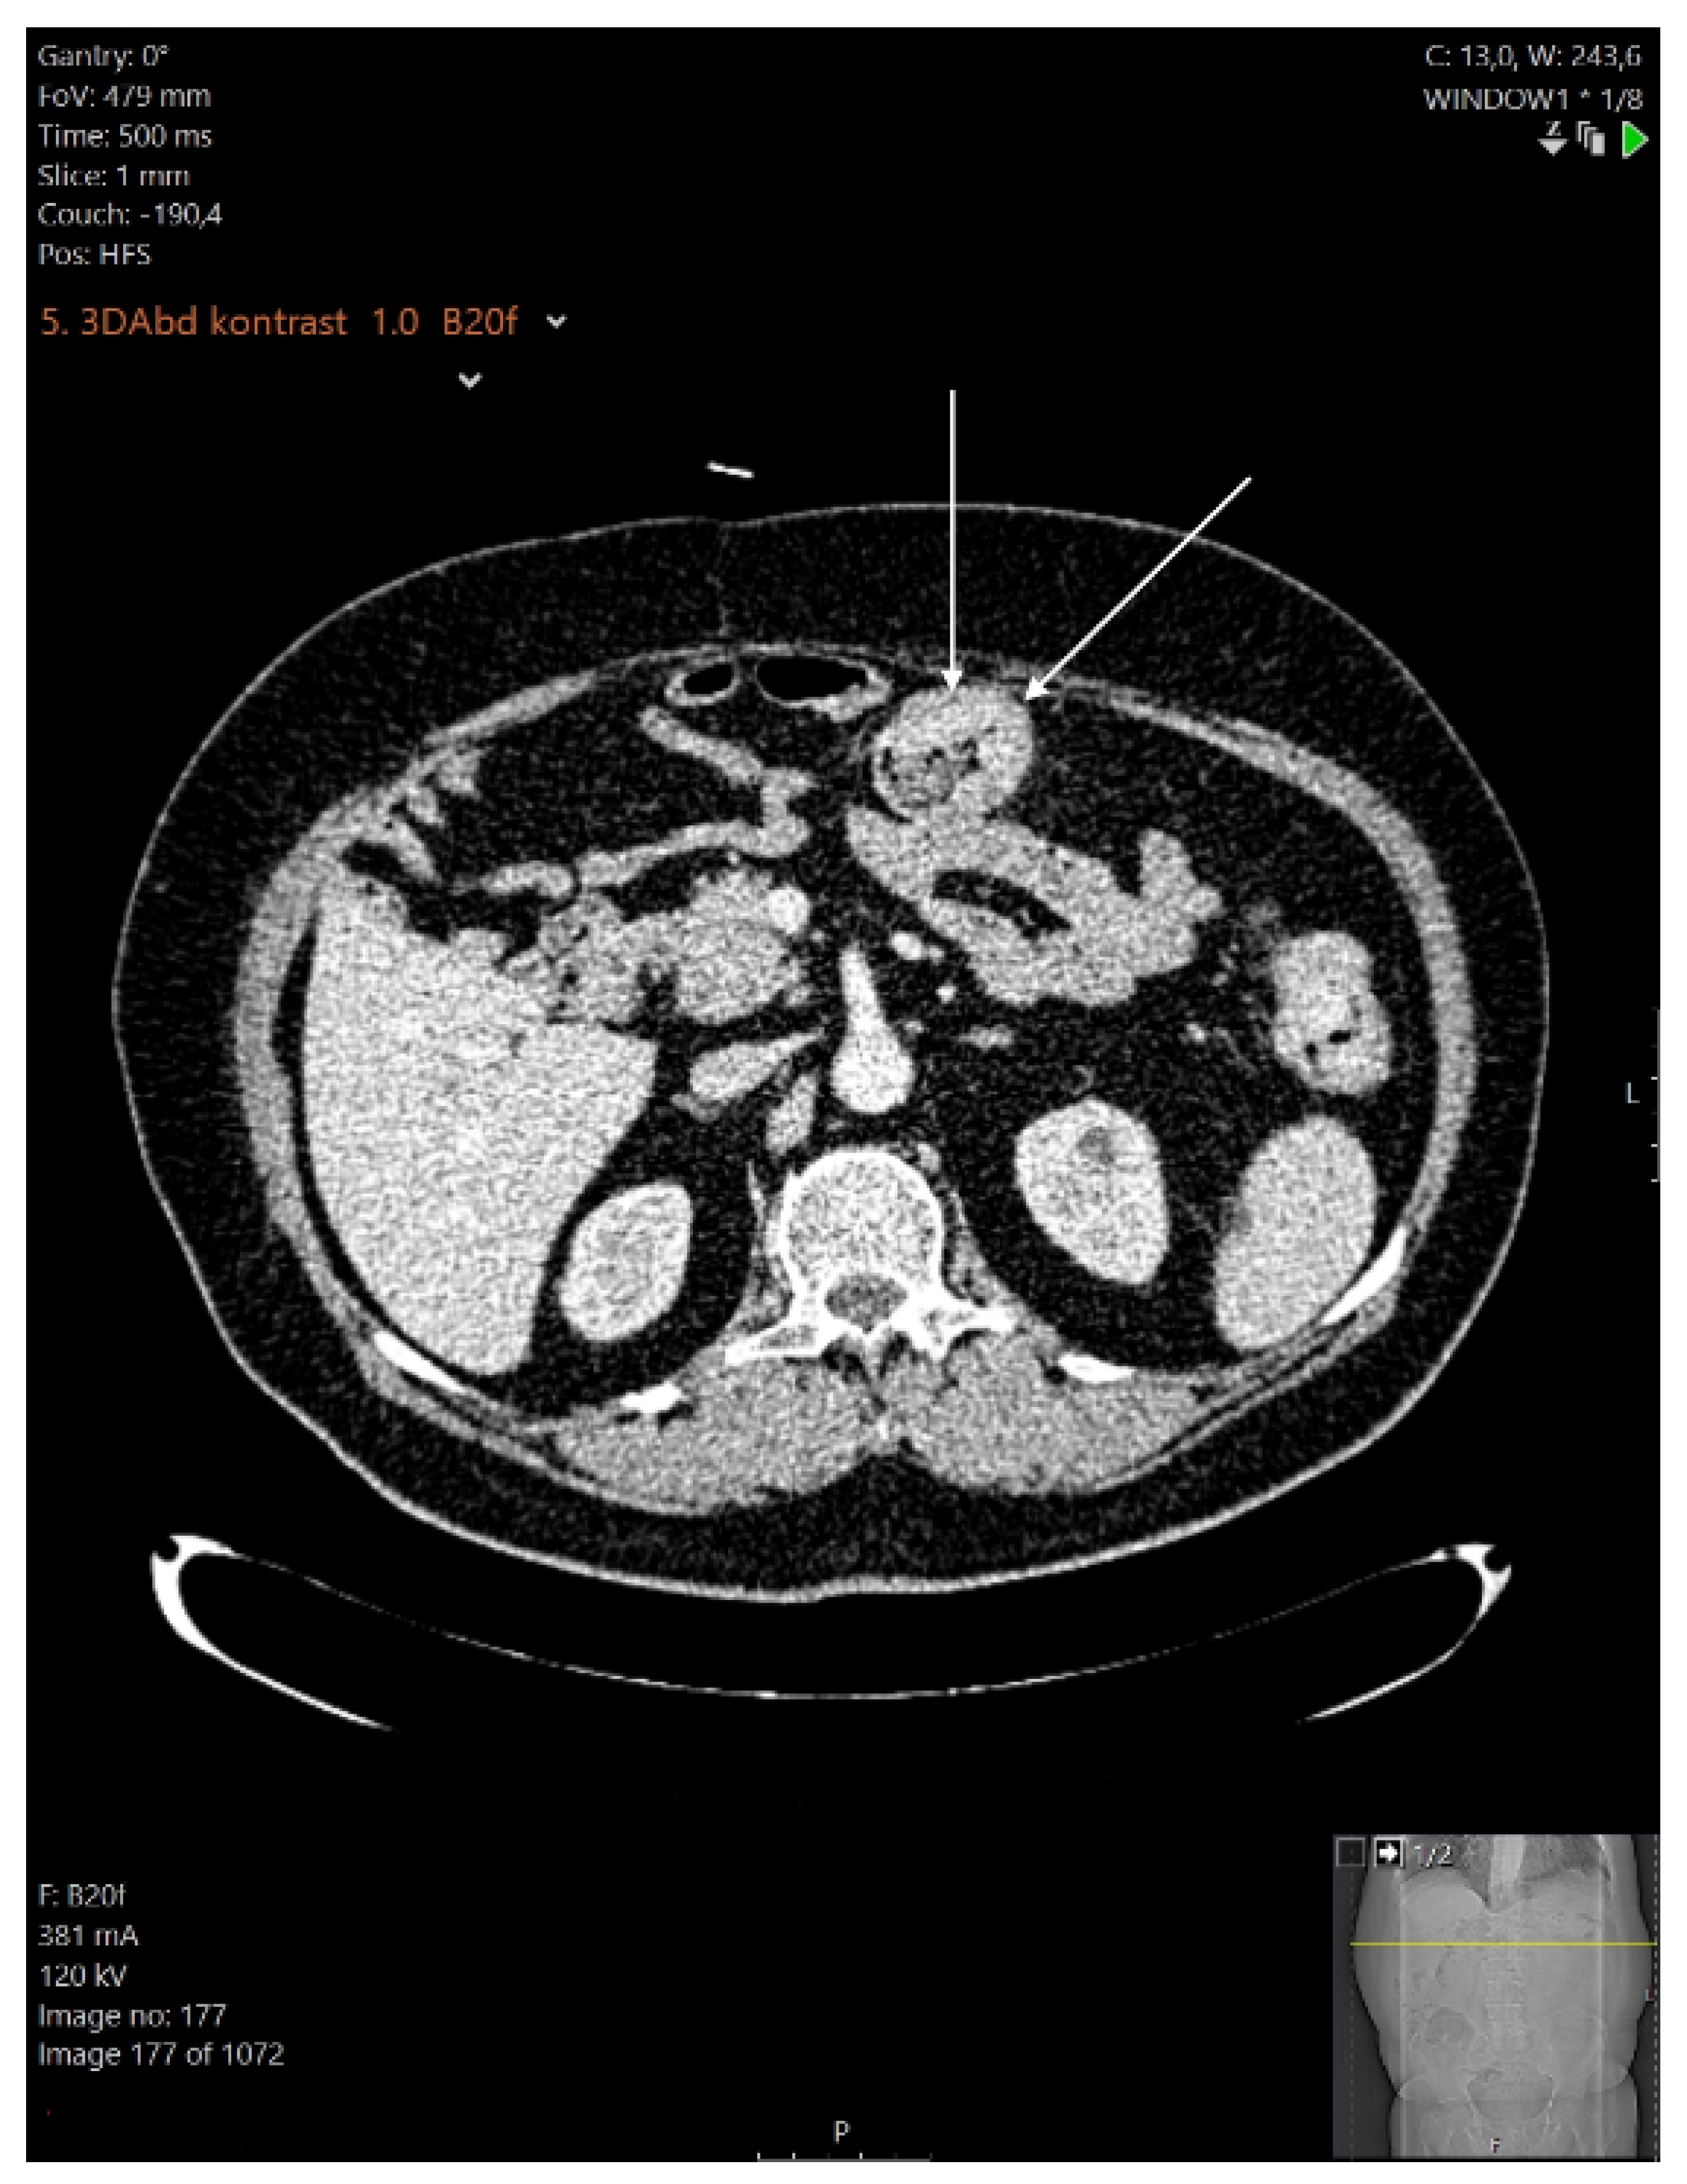

2. Case Report